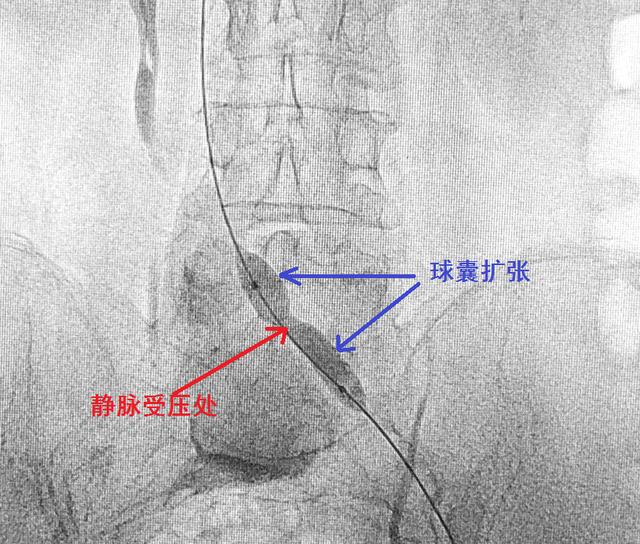

其四,血管成形术。主要是指用球囊导管插到已经初步开通但仍然明显狭窄的病变血管部位,然后充盈球囊,使狭窄处被动地扩张,从而恢复血管的腔径。

球囊导管扩张成形术

静脉被堵的症状往往不如动脉被堵有那么突然而明显的症状,特别是疼痛一般不明显。下肢静脉被堵的最常见原因是深静脉血栓形成,最常见的症状可算是下肢肿胀了,这是由于血液回流受阻而瘀积在组织间隙中造成的。如果是门静脉被堵,胃肠道也会出现瘀血,后续会形成腹水,也可造成食管胃底静脉曲张,最后可造成破裂引起危及生命的消化道大出血。